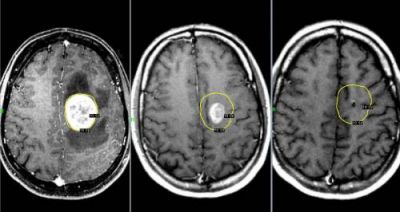

Опухоль мозга

Данное новообразование появляется в тканях мозга и может быть как злокачественным, так и доброкачественным. Последнее можно вылечить без хирургического вмешательства. Злокачественная опухоль растет очень быстро и дает метастазы. Поэтому лечению заболевание поддается с трудом, особенно на поздних стадиях.

При данном заболевании боль ощущается постоянно, а во время движения только усиливается. Самые сильные боли бывают в утреннее и ночное время вследствие накопления избыточной жидкости в тканях. Характер боли — давящий, пульсирующий.

Лечение, проведенное на начальном этапе, имеет намного больший шанс на успех, нежели на поздних стадиях. Почему и рекомендуется не затягивать с посещением лечащего врача. От этого порой зависит жизнь пациента. Как правило, назначается лучевая терапия и определенные медикаменты. В некоторых случаях не удается избежать хирургического вмешательства. Лечение на основе народных средств здесь не помогает. Максимум чего можно добиться —ослабить симптомы.

Опухоли мозга

Злокачественные опухоли характеризуются быстрым прорастанием в другие ткани с их последующей трансформацией. При этом метастазы могут наблюдаться сразу в нескольких участках мозга.

Такие опухоли плохо лечатся, а на поздних стадиях их развития спасти человека практически невозможно.

Клиническая картина

Характер болевых ощущений — постоянный, по мере развития заболевания продолжительность приступов увеличивается. Когда человек двигается, болевые ощущения усиливаются. Сначала они локализуются в области опухоли, потом, по мере увеличения внутричерепного давления, переходят в лобную и затылочную часть. Наиболее сильный дискомфорт наблюдается в ночное и утреннее время из-за скопления жидкости. Вены не справляются с оттоком крови, поэтому к болям прибавляются отёчность и застои. Боли давящие, распирающие, пульсирующие.

К головным болям затем добавляется рвота. При физической нагрузке или кашле болевые ощущения усиливаются, появляется двоение в глазах, временами исчезает зрение. Голова кружится, у пациента нарушается координация движений. Могут неметь конечности, ослабляется тонус мышц.

Иногда бывают эпилептические припадки, путается сознание.

Вмешательство врача

Необходима помощь терапевта, нейрохирурга, онколога, онколога-радиолога.

Диагностирование

Для диагностики используется МРТ мозга, ПЭТ, КТ мозга, ангиография и другие методы.

Лечение

- Для облегчения боли на ранних стадиях заболевания врачи рекомендуют мочегонные препараты и кортикостероиды, с помощью которых удаётся добиться частичного снятия отёка и нормализации кровоснабжения на поражённом участке.

- Удаление опухоли с помощью лазера, эндоскопии и ультразвука.

- Иссечение опухоли. Метод травматичен. Способы иссечения: трепанация черепа или удаление костных фрагментов.